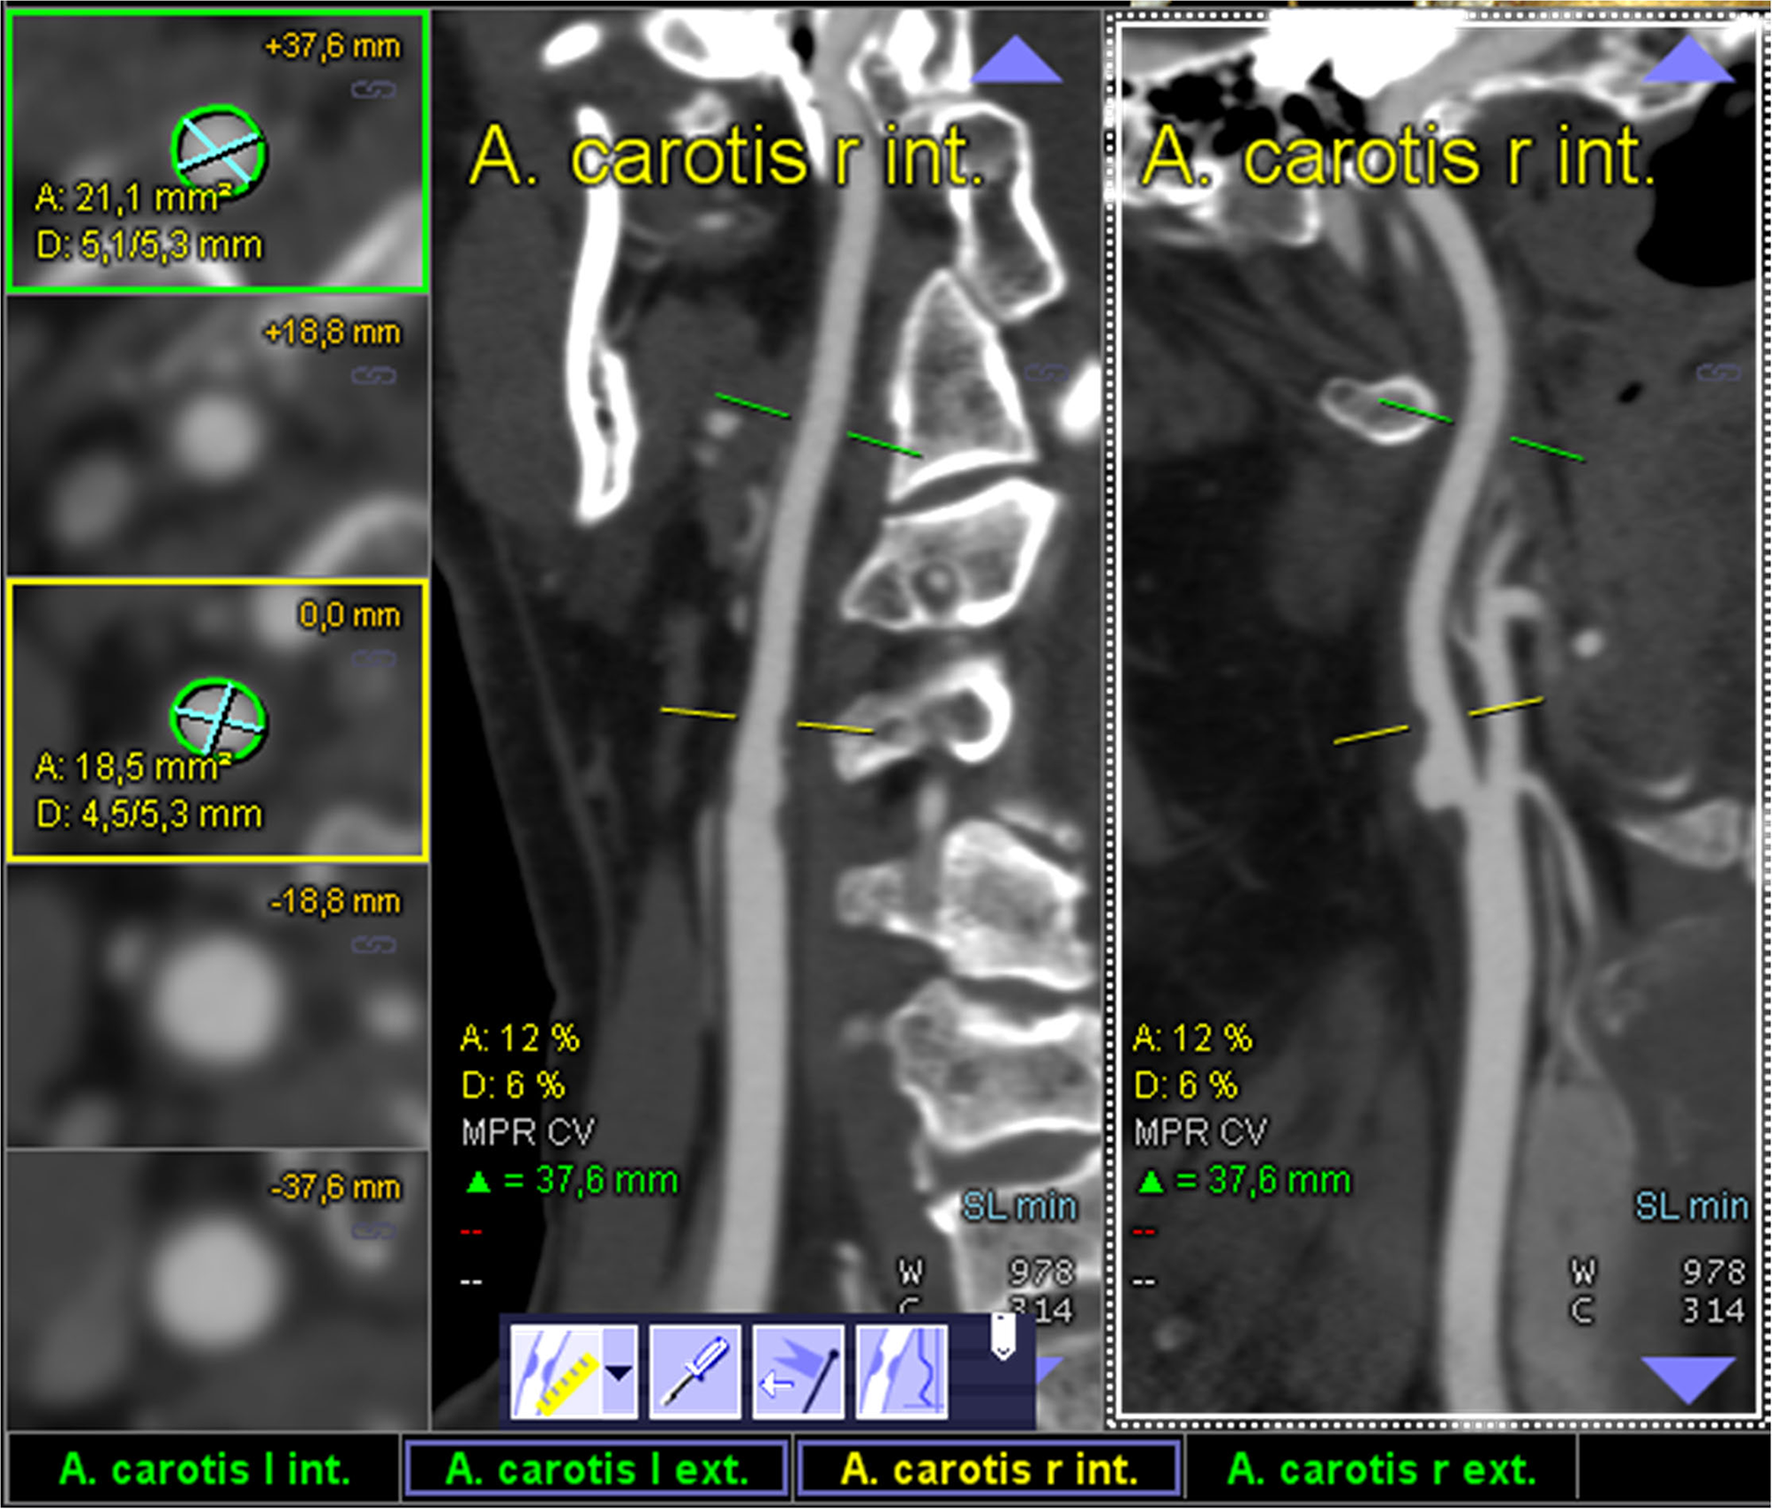

All semiautomated analyses were performed using an image analysis software (syngo.via, Siemens Healthineers, Forchheim, Germany, version VA30A) after preprocessing of the images including contrast optimization and determination of landmarks as previously described (14). This method automatically defined bilateral carotid artery centerlines and provided curved vessel reconstructions. Additional manual adjustments of these centerlines became necessary in case of severe pathologic changes of the stenotic segment, or data quality restrictions. Within the vessel reconstruction, the stenosis was localized and the minimum perpendicular caliber was determined. A second caliber was determined within the closest distal normal appearing ICA segment serving as the reference. The percentage of the stenosis area was finally computed (Figure 2). The center line needed to be adjusted if automatic segmentation of the target vessel failed because of insufficient luminal contrast, extensive calcification, pseudo-occlusion due to stenotic circulation decrement or accidentally in equal measure contrasted veins in proximate distance to the ICA. This was achieved manually by defining the start and end points of the vessel segmentation (Figure 3). The applied contouring algorithm was based on active contour models excluding calcification.

Figure 2

Display of an optimal semiautomated perpendicular stenosis area minimal caliber computation as provided by the “syngo.via” image analysis software: one of the ICAs is automatically detected and the sufficiently contrasted CTA data are displayed as multiplanar reformatted coronal and sagittal view (middle and left column; centerline faded). The segmentally determined luminal area and the underlying non-perpendicular maximum calibers are displayed in the left column (digital caliper).